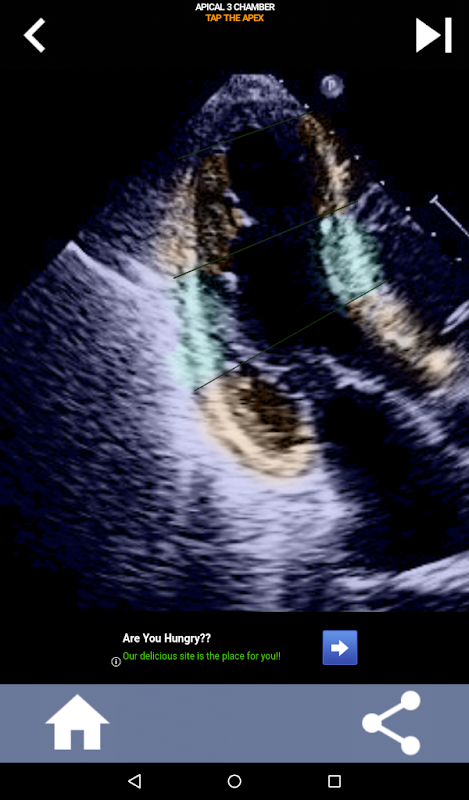

Quizbasierter visueller Ansatz zum Erlernen der AHA-Herzsegmente: Echokardiographie

Diese App testet Ihr Wissen anhand echter Echobilder, was meiner Meinung nach oft die beste Lehrmethode ist.